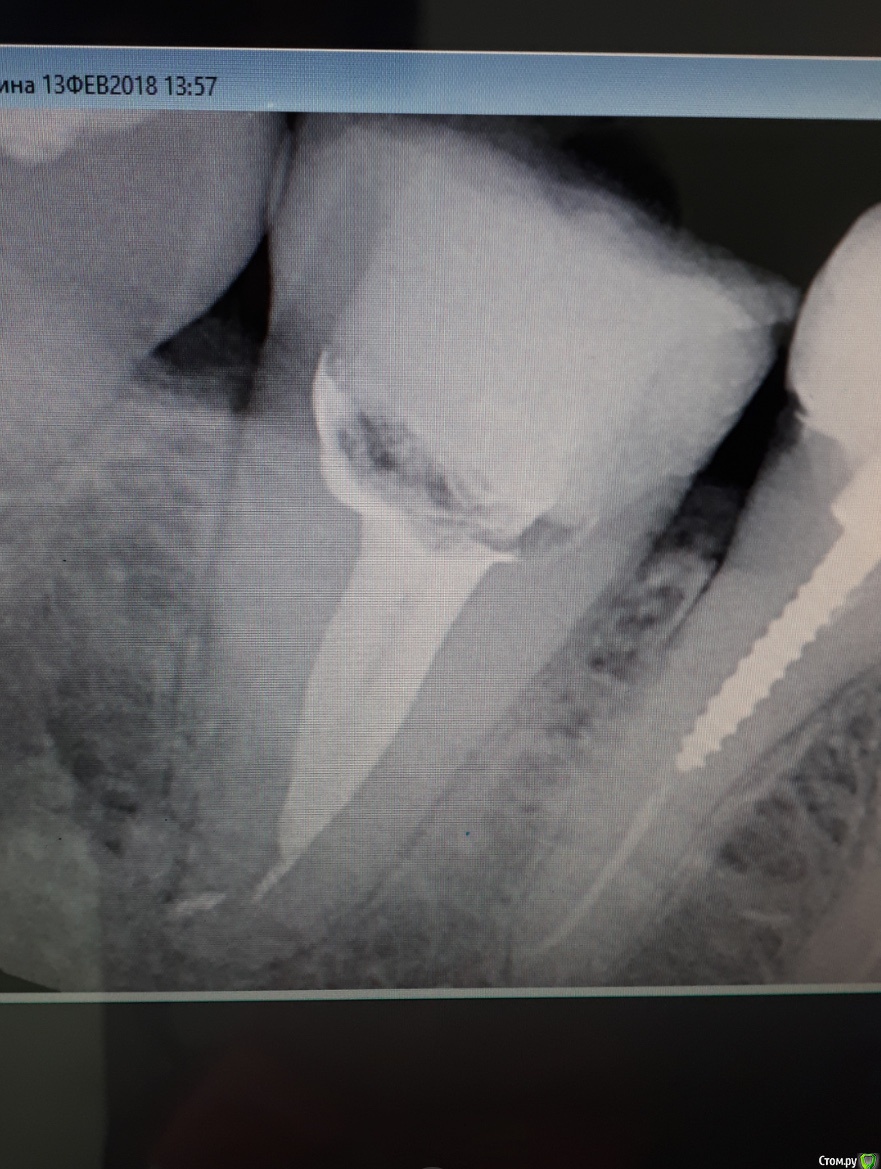

Лана-Лана Опубликовано 15 февраля, 2018 Автор Поделиться Опубликовано 15 февраля, 2018 (изменено) Сейчас зуб в таком состоянии с метапиксом( перепутала изначально сказала метопаста), вижу темное пятно слева от зуба это что воспаление? И так же вижу слева как второй корень именно корень а не канал... он как бы чуть чуть выглядывает из за первого корня , или это наслоение какое то?. в первом корне 2 канала а может быть в другом корне тоже какой то патайной канал которого воачи не видят ? Изменено 15 февраля, 2018 пользователем Лана-Лана Ссылка на комментарий

Лана-Лана Опубликовано 17 февраля, 2018 Автор Поделиться Опубликовано 17 февраля, 2018 Зуб стал болеть с метапиксом такая давящая ноющая, припухлость не уходит! Что делать дальше? Ждать ? Сказали ходить три недели! Или пойти поменять лекарство? Уважаемые доктора посмотрите последний снимок почему лекарство не до апекса? Оно вообще как то подействует на воспаление в кости в десне? Может ли быть в таком зубе третий канал скрытый? Может какой то внутри разделяется на два? По кт может что то видно? Ссылка на комментарий

DmitrySH Опубликовано 21 февраля, 2018 Поделиться Опубликовано 21 февраля, 2018 почему лекарство не до апекса? Оно вообще как то подействует на воспаление в кости в десне? По снимкам вся работа достаточно прилично выглядит. Паста в каналах не обязательно должна доходить до верхушки. Мы не действуем за пределами зуба. Задача эндодонтического лечения сводится к максимальной дезинфекции каналов. А то что творится вне зуба, уже сам организм должен справляться. Ссылка на комментарий

St. Опубликовано 22 февраля, 2018 Поделиться Опубликовано 22 февраля, 2018 Организм каждого человека индивидуальный и к сожалению не всегда можно спрогнозировать как он себя поведет в той или иной ситуации. Все что может сделать доктор - это максимально качественно и ответственно следовать современным протоколам лечения. По приложенному снимку работа выглядит прилично. Ссылка на комментарий